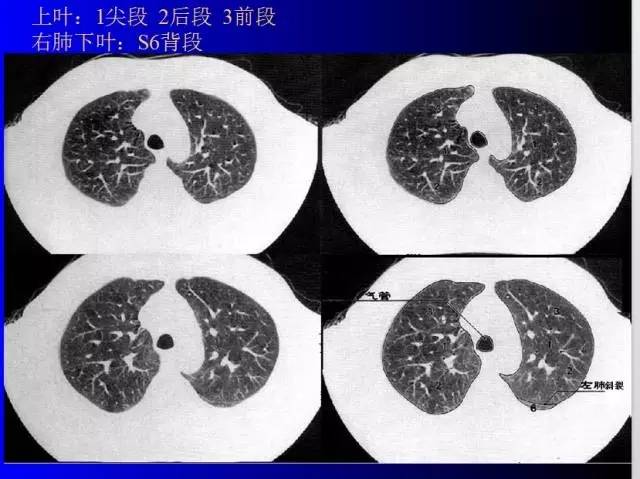

肺部基础X片及CT片解读